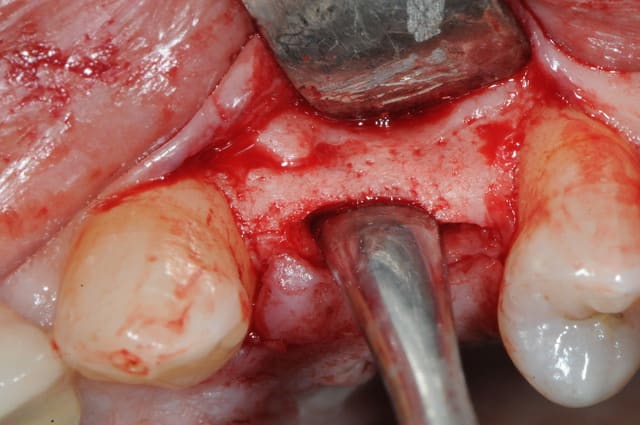

dis moi la tu le trouves comment mon compromis avec l'espace biologique

eii

d'après toi faites il y a combien de temps?

Superbe ratrapage suite à une operculisation d'une vis de couverture. Félicitations. Je te savais costaud béotien mais là tu m'impressionnes vraiment.

- pas de vis de couverture , pas d'operculisation!!

Même pas de lambeau pédiculé palatin!